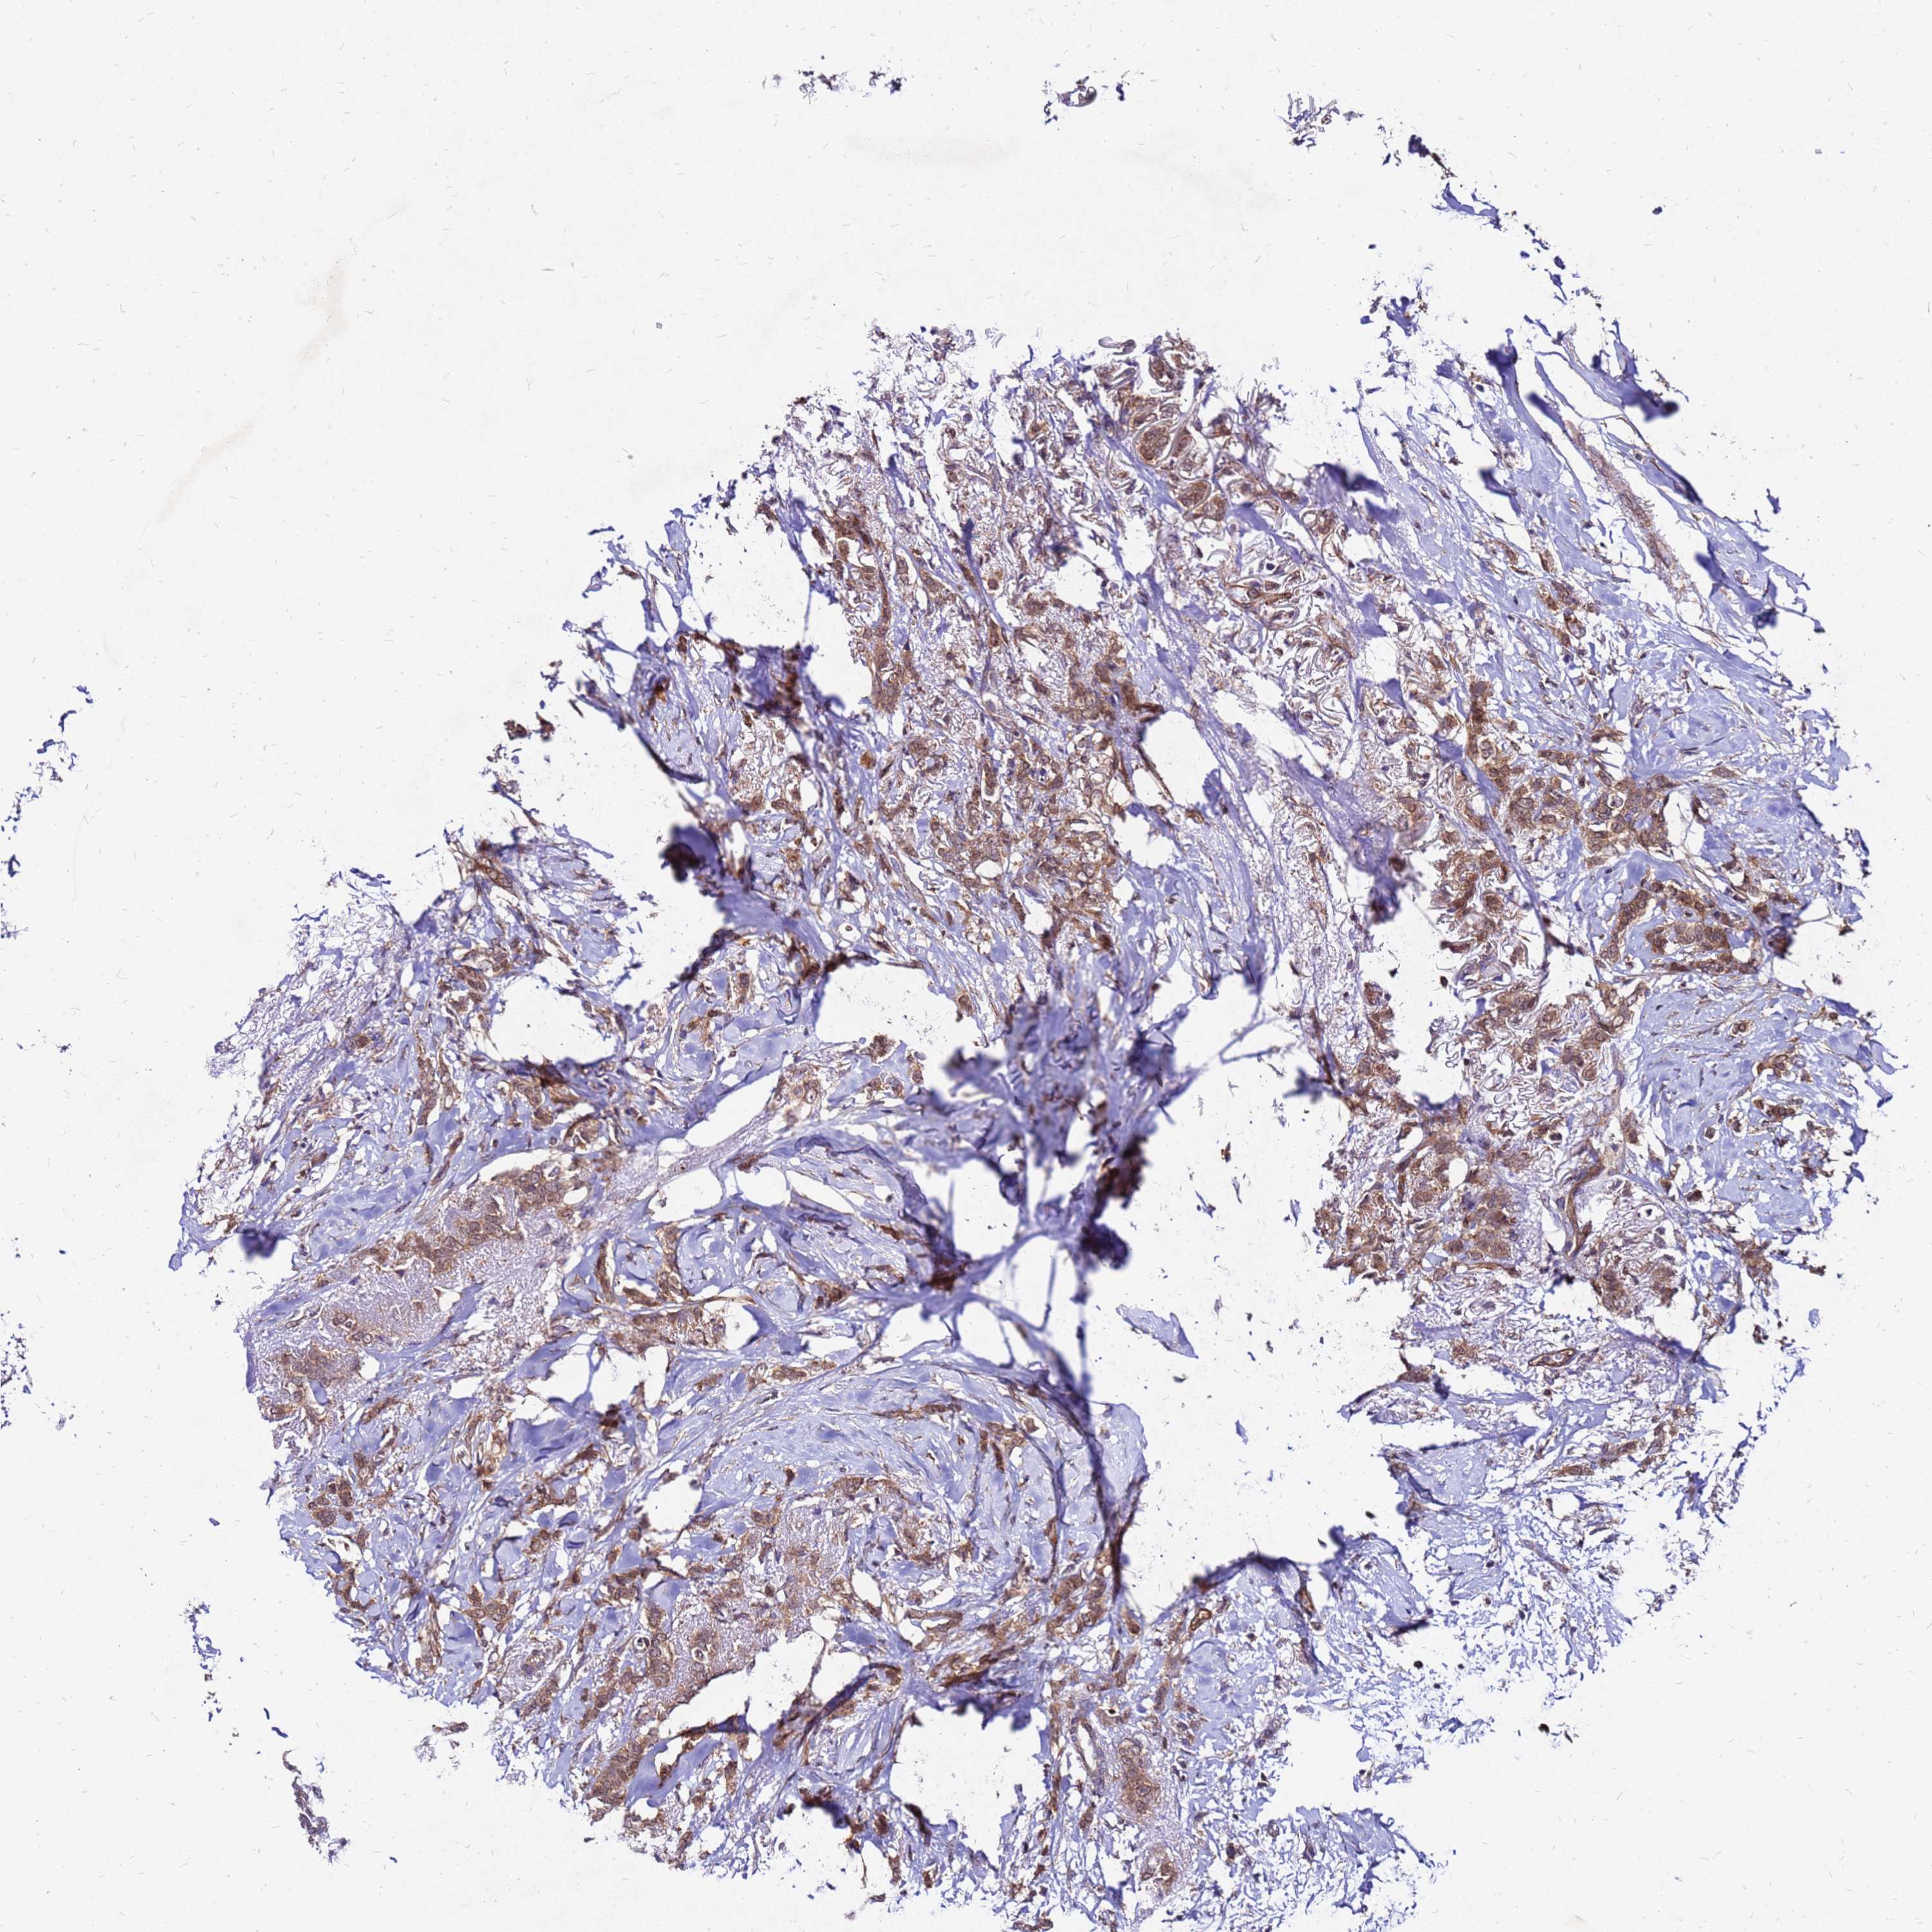

BRCA TCGA BRCA VALIDATION PROTEIN EXPRESSION

ANTIBODIES

AND

VALIDATION